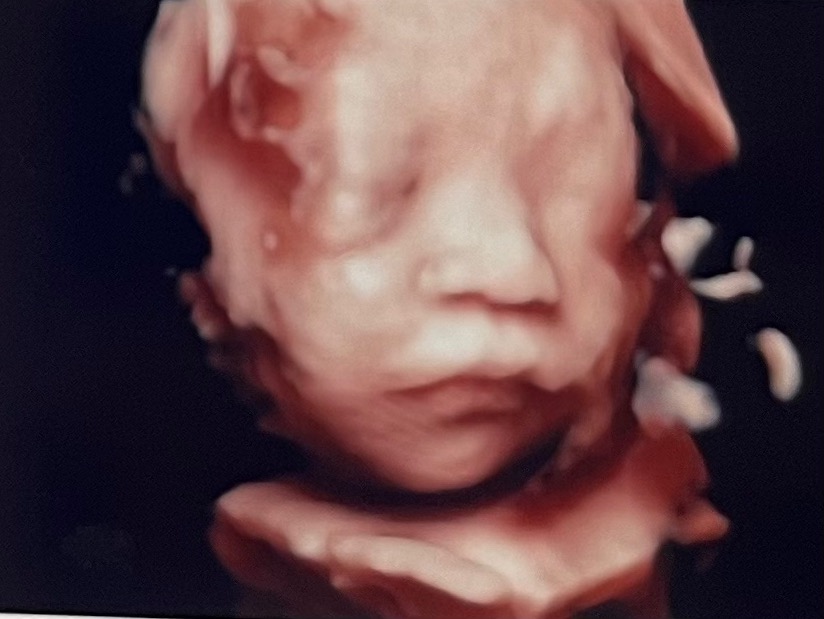

[결과 및 후기] 얼굴 보기 성공!!

처음에 저희 아가는 한쪽 팔을 들어

턱 한쪽을 막고있는 형태로 있더라구요?

그래서 조마조마했는데

선생님이 노련하신건지, 제가 운이 좋은건지,

아기가 현재 어떤 형태로 자리잡고있는지에

기반해서 제 자세를 이리 저리 조정해주시더니

결국 ㅎㅎㅎ 보고야말았습니다!!!!

(아기얼굴 보일때의 제 자세는 왼쪽으로 누운

상태에서 거의 엎드리다시피한 각도로 벽을

잡고 지탱하는 모양새였고, 선생님은 제

오른쪽 옆구리를 거의 등뒤에서비춰서??

보시는 중이었어요, ㅎㅎㅎ)

진짜 많이 컸더라구요!

미국에서는 19-20주 2차 정밀 초음파가

끝이라서 그 이후로 처음 보는 아가였는데,

진짜 아기같은 모습이 다 갖춰져서

너무 반갑고 감격스럽고 행복했어요!

친정 엄마께도 오히려 찰흙외계인 모습이 아닌

굉장히 아가아가한 모습을 보여드릴 수 있어

좋더라구요! ㅎㅎ 엄마는 저 가졌을땐 이런게

없었다며 엄청 신기해하시고 신나하셨어요!

머리끝부터 발끝까지 건강상태 체크하면서

심지어 아가가 하품하는 모습까지 잡혔는데!!

심쿵사!! ♥ 진짜 너무 귀엽습니다 ㅎㅎㅎㅎ

아! 원장님께서 검사결과 면담해주실때

제일 먼저 하신말씀이 정면으로 보면 코가

낮아보여서 엄마들이 많이 실망하는데,

이 사진으로 보면 원래 다 그렇다,

양수에 불어있어서 그렇기도 하고 정면샷은

더욱 더 그렇기도 하니까 미리 실망안해도 된다

하시더라구요! 실제로 옆모습나온 사진은

코가 있습니다 있어!! ㅎㅎㅎ